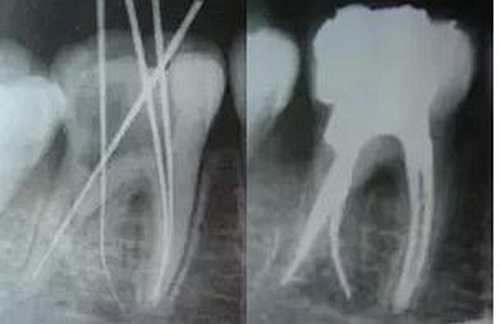

最后來(lái)玩一個(gè)根管治療質(zhì)量的評(píng)估——下圖是武大彭彬教授的一個(gè)病例,仔細(xì)觀察可以挑出一點(diǎn)問(wèn)題,但問(wèn)題事出有因!看看你的“眼力”如何——問(wèn)題在那里?教授的專(zhuān)業(yè)水平是不用懷疑的,那么事出的原因可能是什么?

問(wèn)題答案:這個(gè)病例的問(wèn)題主要反應(yīng)在開(kāi)髓的洞形修整,注意觀察該牙X-RAY的左側(cè)洞壁,如果常規(guī)情況制備成這樣是由于裂鉆破壞了洞壁和洞底所形成的臺(tái)階。如果評(píng)估根管治療的質(zhì)量那是要扣分的!但這個(gè)病例仔細(xì)觀察洞壁形態(tài)就可以看出:該病例屬于再治療的病例,因此還是屬于一個(gè)理想的病例。